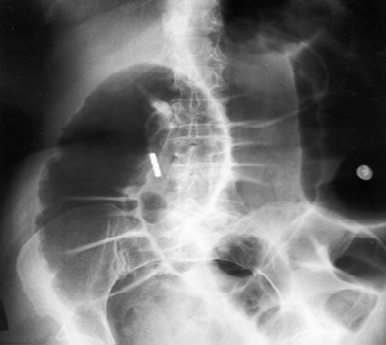

• Μεγάλη διάταση παχέος εντέρου σε απλή ακτινογραφία.

• Απουσία μηχανικής απόφραξης στο βαριούχο ή στον υποκλυσμό με γαστρογραφίνη (προτιμάται).